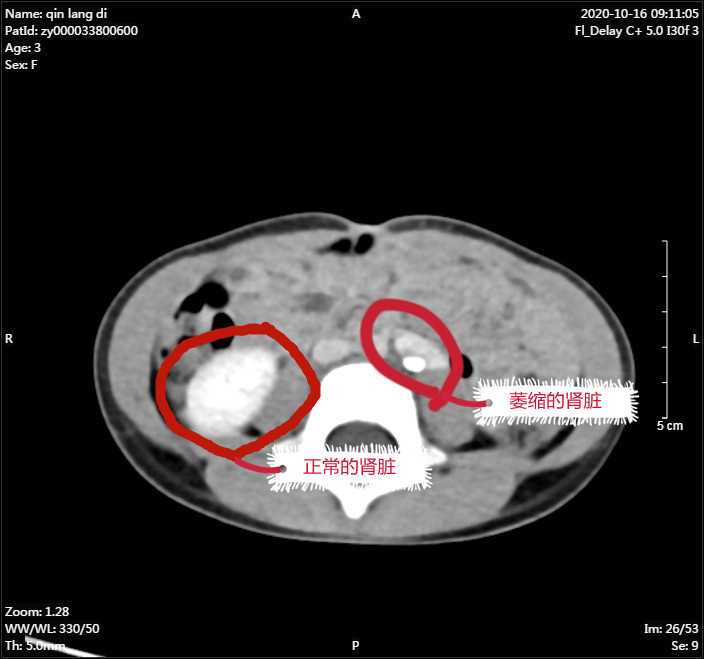

据了解,朗朗父母发现不给朗朗使用尿布湿后,孩子竟然天天漏尿,且伴有尿频、尿急症状,长达7个多月,给日常生活带来极大困扰,遂带他来到我院泌尿外科就医。经检查,朗朗被确诊为左肾异位伴萎缩伴左输尿管口异位,即先天性的输尿管开口异常。这是小儿常见的泌尿系统畸形,病因大多是胚胎时期输尿管芽发育异常,往往伴随其他器官发育不良,如重复肾、双重输尿管等,需要根据异位开口类型、引流肾脏功能选择合适的手术方式进行治疗。

朗朗的左侧肾脏不在正常位置,而且已经萎缩得极小,直径仅1.5厘米,已丧失基本功能,取得家属同意后,泌尿外科医疗团队决定切除左肾及部分输尿管。然而,如何精确的找到肾脏,减少不必要的损伤,又能达到术后快速康复及术口美观的效果,成了困扰泌尿外科医疗团队的一大难题。